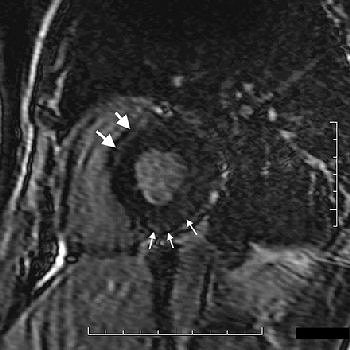

Moving on to the heart, cardiac complications in Fabry's disease may include left ventricular hypertrophy and a short PR interval on ECG. MRI can be employed to diagnose angina pectoris, atrioventricular block, and mitral valve prolapse.

| Cardiac involvement in 38-year-old man. Late-enhancement T1-weighted cardiac image in short axis (1.5-tesla system, 3D inversion recovery T1-weighted multishot gradient echo; TR/TE, 3.9/1.4; flip angle, 25°; inversion-recovery prepulse delay, 200 msec) shows band of hyperenhancement assumed to be related to myocardial fibrosis in upper part of septum (large arrows) and subepicardial nodules in inferior wall (small arrows). Cine MRI image at same level (not shown) displayed normal segmental contraction. |

The imaging protocol "must include cine MRI steady-state free-precision sequences in short-axis, long-axis, and four-chamber views; and delayed-enhanced T1-weighted sequences in at least the short-axis view," the authors stated (AJR, April 2006, Vol. 186:4, pp. 1184-1191).

Almost all Fabry's disease patients -- men in particular -- display left ventricular (LV) hypertrophy, brought on by focal myocardial fibrosis, which gives off an abnormal signal. Lidove's group stressed the importance of measuring LV mass at initial presentation as this information must be monitored as a prognostic indicator of therapy, the group said.